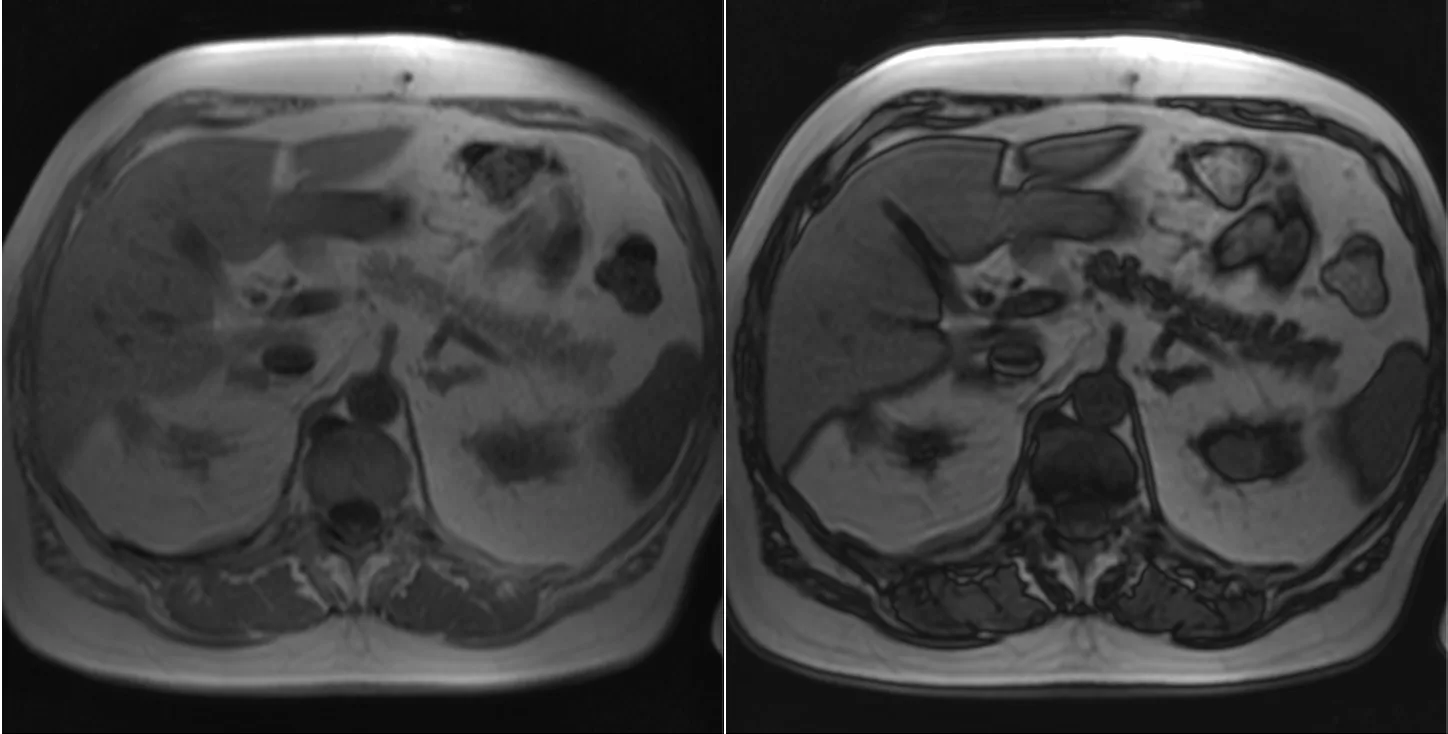

Красивый пример ожирения (стеатоза) поджелудочной железы: на скане вода-жир в противофазе имеется резкое падение сигнала её паренхимы. Интересно, что значимого ожирения печени у пациента нет. Хотя изолированный стеатоз поджелудочной железы встречается, имеющиеся данные свидетельствуют о том, что это - нетипично. Существует связь между ожирением поджелудочной железы и метаболическим синдромом и это означает, что у большинства пациентов с таким диагнозом также наблюдается или со временем развивается ожирение печени или другие метаболические нарушения, в рамках метаболического синдрома. Однако в одном исследования было обнаружено, что до 1/4 всех случаев стеатоза панкреас не совпрвождаются таковым в печени, авторы делают вывод, что

"неалкогольная жировая болезнь печени не всегда сопровождается неалкогольным стеатозом поджелудочной железы. Несмотря на выраженный стеатоз поджелудочной железы, более чем в четверти случаев эхогенность печени была в норме. Частота инсулинорезистентности при неалкогольной жировой болезни печени была незначительно выше, чем при неалкогольном стеатозе поджелудочной железы (p=0,694). Значительно более высокая частота желчнокаменной болезни при неалкогольном стеатозе поджелудочной железы требует проведения дальнейших масштабных исследований. Несоответствие степени стеатоза печени и панкреас в более чем 50% случаев может отражать различия в патофизиологии этих двух клинических проявлений.